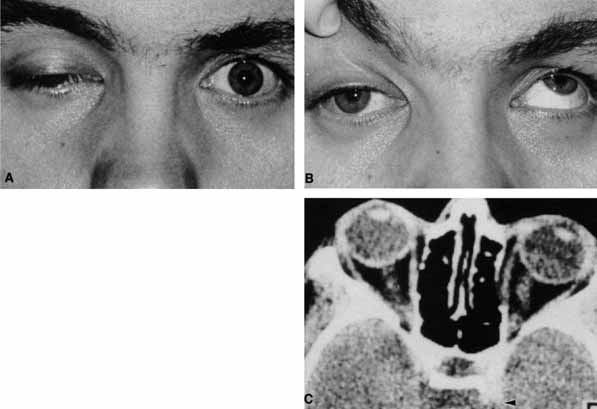

Fig. 19 A. A patient underwent endoscopic exploration of the right ethmoid and maxillary sinus for persistent epistaxis. Postoperatively the patient demonstrates right proptosis, restricted extraocular movements of the right eye, and a dilated right pupil. Instillation of 0.1% pilocarpine resulted in miosis on the right and no change on the left. Computed tomography (CT) shows a vessel clip lateral to the optic nerve (arrow), near the position of the ciliary ganglion. B. Coronal CT scan showing the clip lateral to the optic nerve (arrow).

Damage to parasympathetic fibers proximal to the ciliary ganglion also results in a dilated pupil but without the susceptibility to 0.1% pilocarpine. Trauma, surgery, inflammation, and intracranial aneurysms may produce a dilated pupil. Damage to the parasympathetics proximal to the ciliary ganglion is usually associated with ptosis and third cranial nerve ophthalmoplegia.